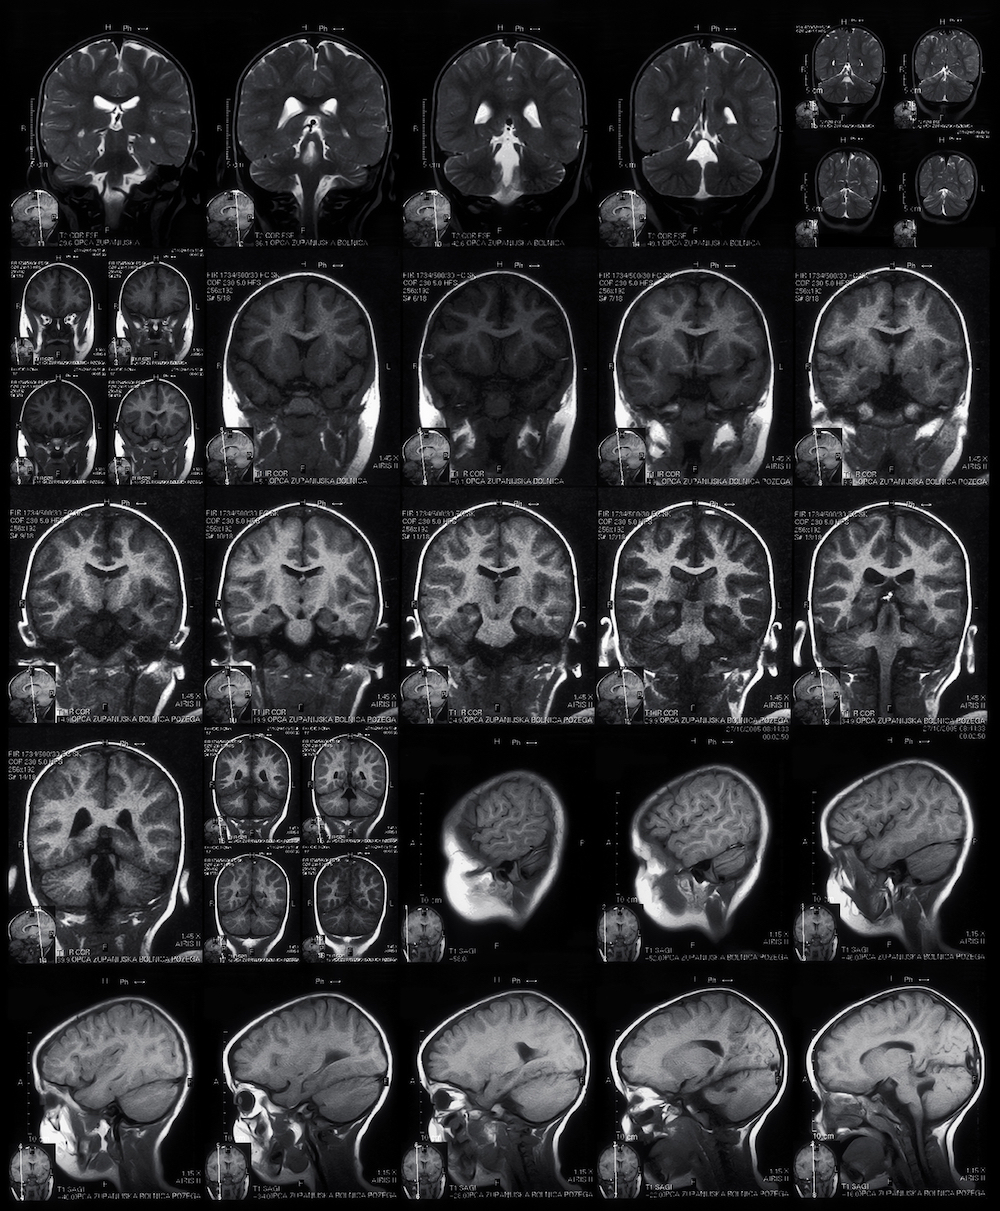

Cat Scan For Concussion. A ct scan takes pictures to create images of the brain. Learn how a ct scan can show a head injury and how imaging helps your physician learn more about a recent or past head injury or concussion.

Loss of consciousness >60 seconds. However if there are signs and symptoms that suggest a more serious injury, such as an intracranial bleed, a ct scan is the test of choice in the first 24 to 48 hours. If the concussion appears severe, an mri or ct scan is done.

A Ct Scan Of The Brain Is Meant To Look For Serious Things Like Bleeding In The Brain, Atabaki Says.

An mri creates clear images of brain tissue. The use of ct scans in diagnosing concussion is surprisingly common among neurologists. Presenting within 24 hours for isolated closed head injury.

But These Scans Cannot Show If You Have A Concussion.

For these procedures, the animal is given general anesthesia. That’s because a concussion cannot be detected o a ct scan or brain mri. But your child may not need a ct scan for a minor head injury.

Patients And Their Families Often Ask When A Cat Scan Is Appropriate For Those Who Have Had A Concussion.

What Mris & Ct Scans Reveal.